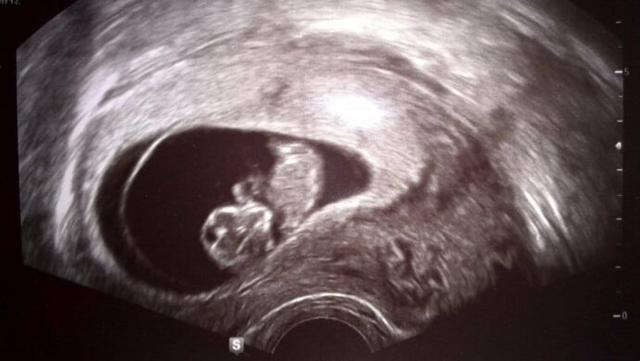

Im ersten Schwangerschaftsdrittel, genauer gesagt ab der 6. Woche, ist der Herzschlag des Embryos bereits auf dem Ultraschall sichtbar. Dies ist ein wichtiger Meilenstein in der Entwicklung des Fetus und ein erster Hinweis darauf, dass alles gut verläuft. Der Herzschlag kann dann auch regelmäßig überprüft werden, um sicherzustellen, dass das Kind sich normal entwickelt.

Es ist wichtig zu beachten, dass die Schwangerschaftswochen (SSW) nicht mit den tatsächlichen Wochen seit der Befruchtung übereinstimmen. Da die Schwangerschaft ab dem ersten Tag der letzten Regelblutung berechnet wird und die Befruchtung erst etwa zwei Wochen später stattfindet, ist der Embryo oder Fetus immer zwei Wochen jünger als die angegebene SSW vermuten lässt.

Der Ultraschall ermöglicht es den Ärzten, den Entwicklungsstand des Fetus genau zu beobachten und mögliche Probleme frühzeitig zu erkennen. Es ist eine nicht-invasive Methode und daher für Mutter und Kind sicher. Der Herzschlag ist ein wichtiger Indikator für die Gesundheit des Babys und gibt den Eltern auch ein Gefühl der Sicherheit.